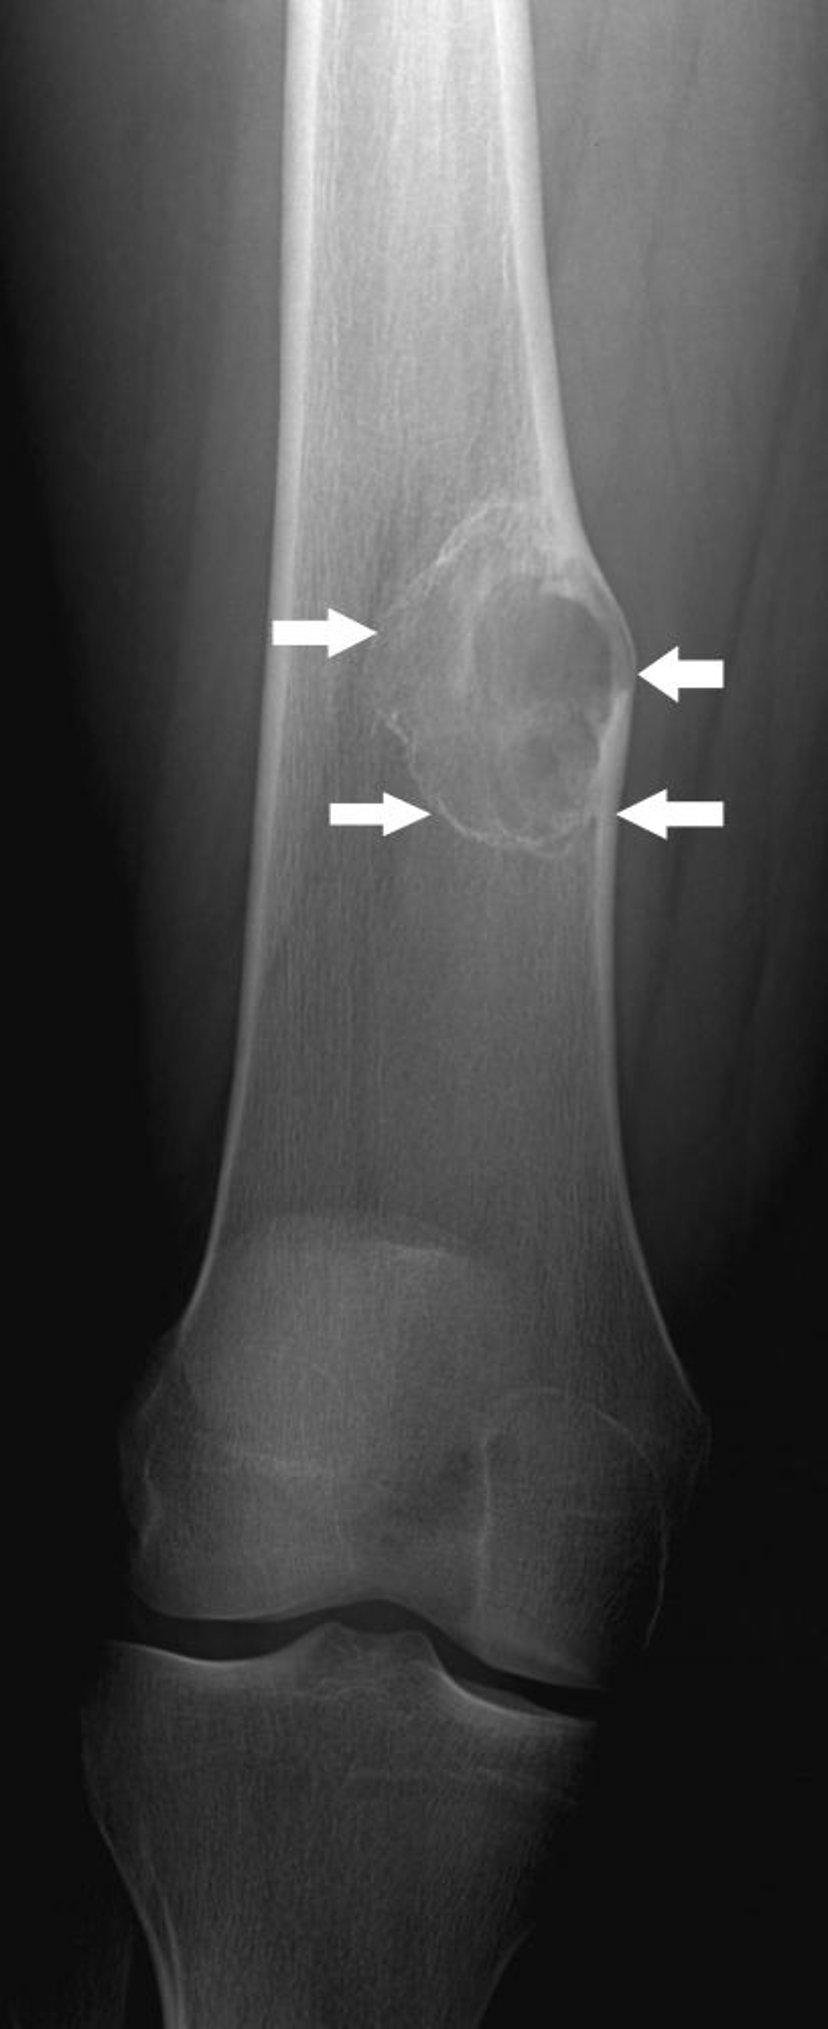

تُظهر هذه الصورة للركبة ورمًا عظميًا غضروفيًا، وهو نمو على سطح عظم الفخذ (اتجاه السهم) فوق مفصل الركبة.

جرى استخدام الصورة بعد موافقة أصحابها Michael J.Joyce, MD, and Hakan Ilaslan, MD.